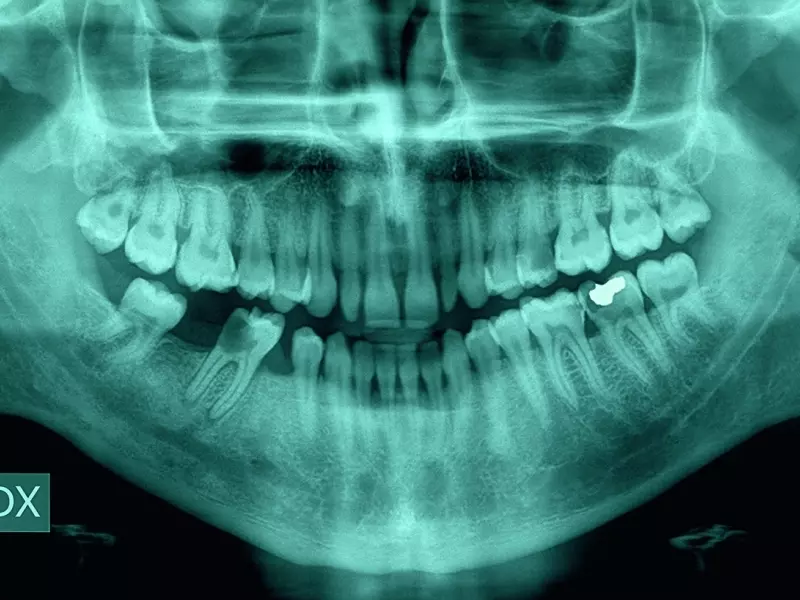

Podczas zabiegu ekstyrpacji żywej miazgi dochodzi do usunięcia głównego pęczka naczyniowo-nerwowego. W bocznych rozgałęzieniach mogą pozostać resztki tkanki miazgowej, które wskutek pozbawienia dopływu krwi ulegają obkurczeniu i wycofaniu w głąb kanalików. W wyniku tego wewnątrz kanalików zębinowych ma się do czynienia z obumarłą, ale nie zainfekowaną miazgą. Z kolei wskutek toczącego się procesu zapalnego miazga traci swoją strukturę i na powierzchni zębiny pojawiają się luźne, nekrotyczne jej fragmenty. W wyniku współistniejącej infekcji bakteryjnej fragmentacja tkanki miazgowej jest bardziej nasilona. Obraz mikroskopowy ścian kanału przypomina powierzchnię pokrytą warstwą „szlamu” maskującego ujścia kanalików zębinowych. W miarę postępu zapalenia ognisk martwicy jest coraz więcej.

W kanałach zainfekowanych koncentrują się one najczęściej w części koronowej zęba. W części kanałowej jest ich znacznie mniej, szczególnie w przypadku zapaleń przebiegających przy zamkniętej komorze i obecności resztek żywej miazgi w okolicy apikalnej. W części wierzchołkowej korzenia (około 5 mm od wierzchołka) obraz mikroskopowy pokazuje mniej liczne kolonie bakteryjne zawieszone w świetle kanału, a znacznie rzadziej zbite kolonie przyczepione do jego ścian.

Obecność kolonii bakteryjnych na całej długości kanału korzeniowego obserwuje się w przypadku obecności zmian zapalnych w tkankach okołowierzchołkowych.